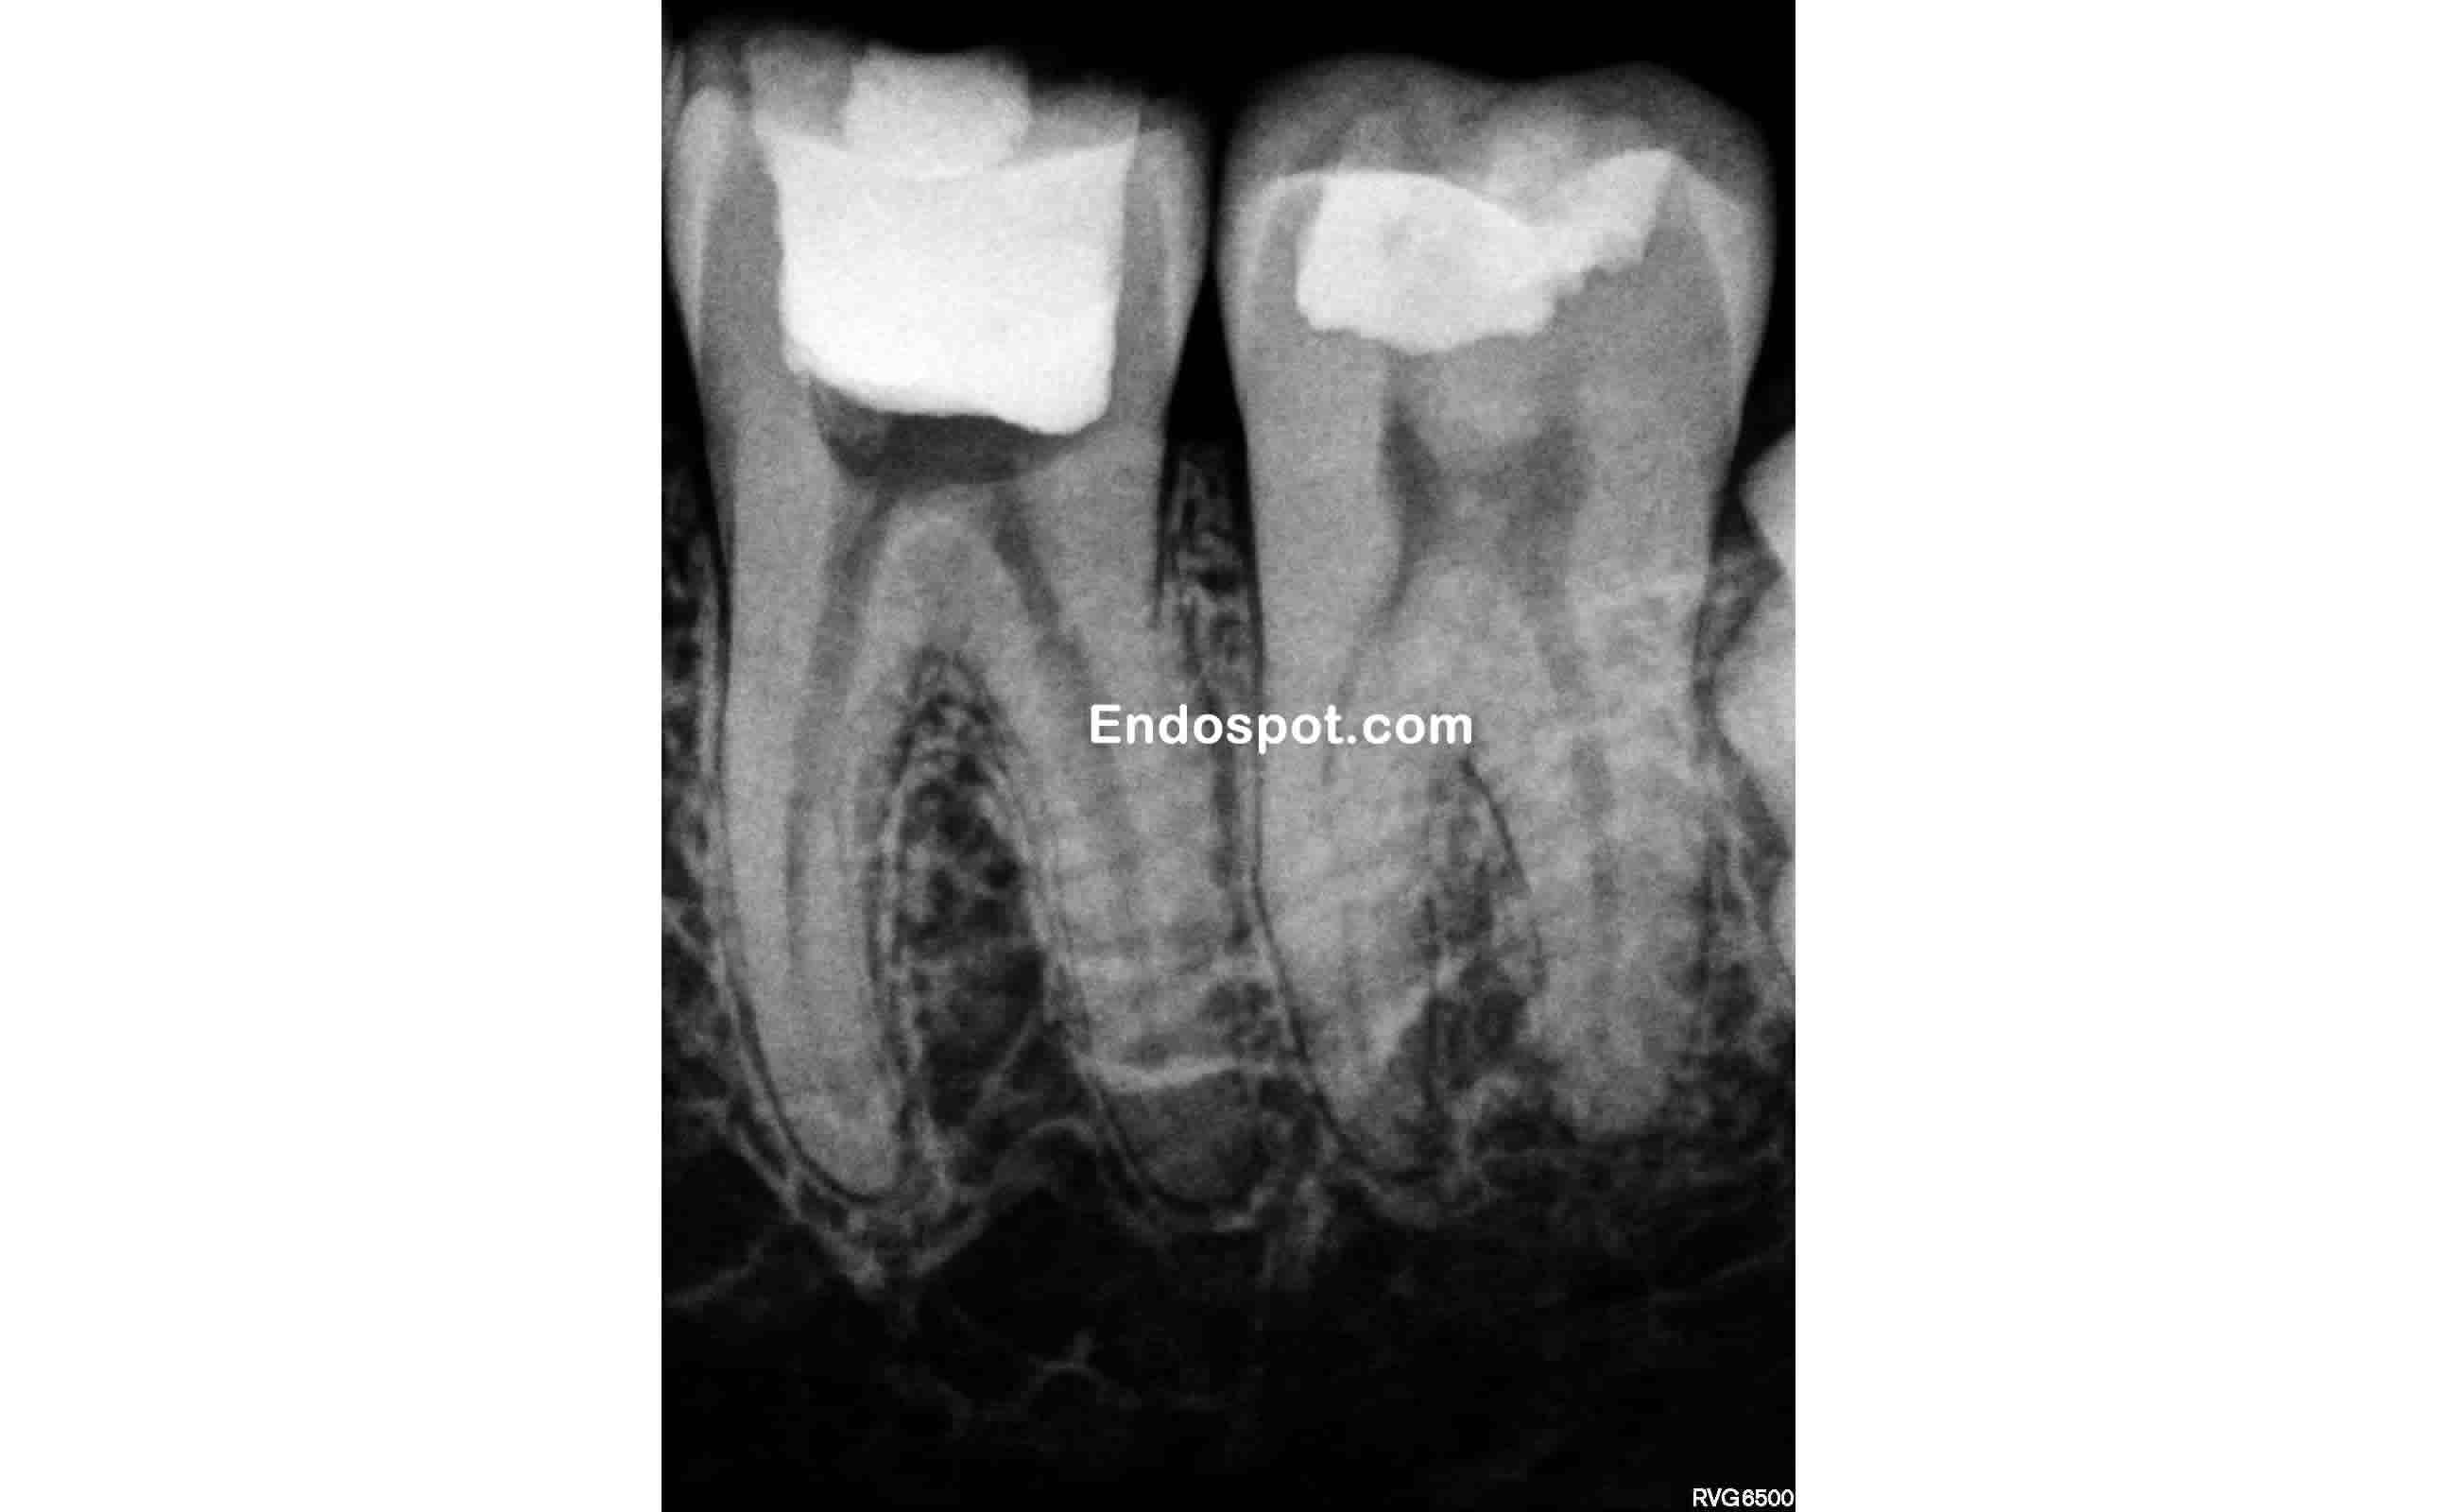

From endospot.com

Endodontic Access for Conservationists. A How To Guide. the endospot Endodontic Access The aim of this paper is to present a simple guide to preparing access cavities in molar teeth, and how to identify and avoid potential. This narrative review aims to discuss the advantages and limitations of methodologies used in these laboratory experiments and to discuss the present status and future directions of studies. An endodontic access cavity (eac) is the. Endodontic Access.

Endodontic Access for Conservationists. A How To Guide. the endospot Endodontic Access The british endodontic society provides guidelines for good endodontic practice, covering topics such as case difficulty assessment, record keeping,. This narrative review aims to discuss the advantages and limitations of methodologies used in these laboratory experiments and to discuss the present status and future directions of studies. The aim of this paper is to present a simple guide to preparing. Endodontic Access.